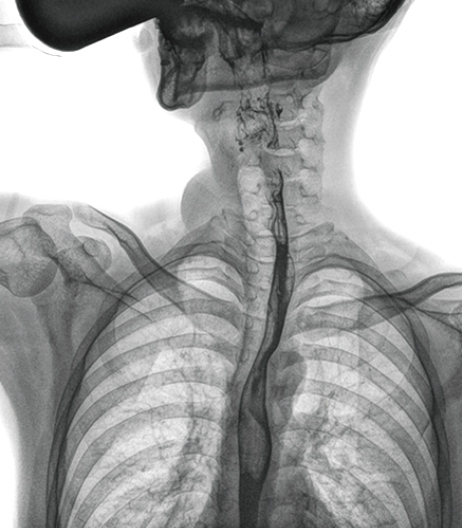

食管造影是食管病變的基本檢查方法,可以發(fā)現(xiàn)食管癌的特征性改變——食管粘膜的中斷和破壞,病人常感覺吞咽障礙,此特征在臨床中最常見,也是早期食管癌的典型表現(xiàn)。一般伴隨的特征有管壁充盈缺損、龕影、軟組織塊影、食管腔狹窄等;在透視下還可看到食管壁僵硬、蠕動(dòng)緩慢等。

在食管造影檢查中,由于吞咽鋇劑后,造影劑流速非??欤瑒?dòng)態(tài)DR影像采集幅面大,普利德多功能動(dòng)態(tài)DR 17×17英寸超大視野,一次曝光即可顯示整個(gè)食管,更方便觀察食管的病變,確定病變的范圍,對(duì)診斷和治療有重要參考價(jià)值。

動(dòng)態(tài) DR 可以動(dòng)態(tài)觀察管壁蠕動(dòng)是否僵硬,以鑒別良、惡性狹窄,不但在透視過程中,可實(shí)時(shí)高清點(diǎn)片,實(shí)現(xiàn)毫秒級(jí)動(dòng)靜態(tài)圖像切換,快速捕捉病變部位的影像,成像清晰而迅速,盡可能減少食管功能性障礙患者因吞咽困難而忍受痛苦的時(shí)間,同時(shí)提高醫(yī)生做出正確診斷的效率,還能實(shí)時(shí)保存視頻影像,反復(fù)觀察、分析,明確病變范圍,對(duì)手術(shù)有重要的指導(dǎo)意義。

與過去的數(shù)字胃腸機(jī)比較,動(dòng)態(tài)DR圖像分辨率高,對(duì)食管的全景觀察,局部粘膜破壞、中斷,管腔狹窄以及病灶范圍的顯示清晰度明顯更優(yōu)。

上消化道造影高清圖像